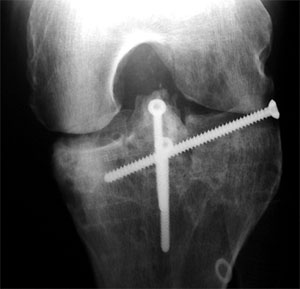

Die neue Konstruktion von vorne bei ca. 45° gebeugtem Knie. Rechts von der Eminenz ist einer der frischen Schnitte im Knochen sichtbar.